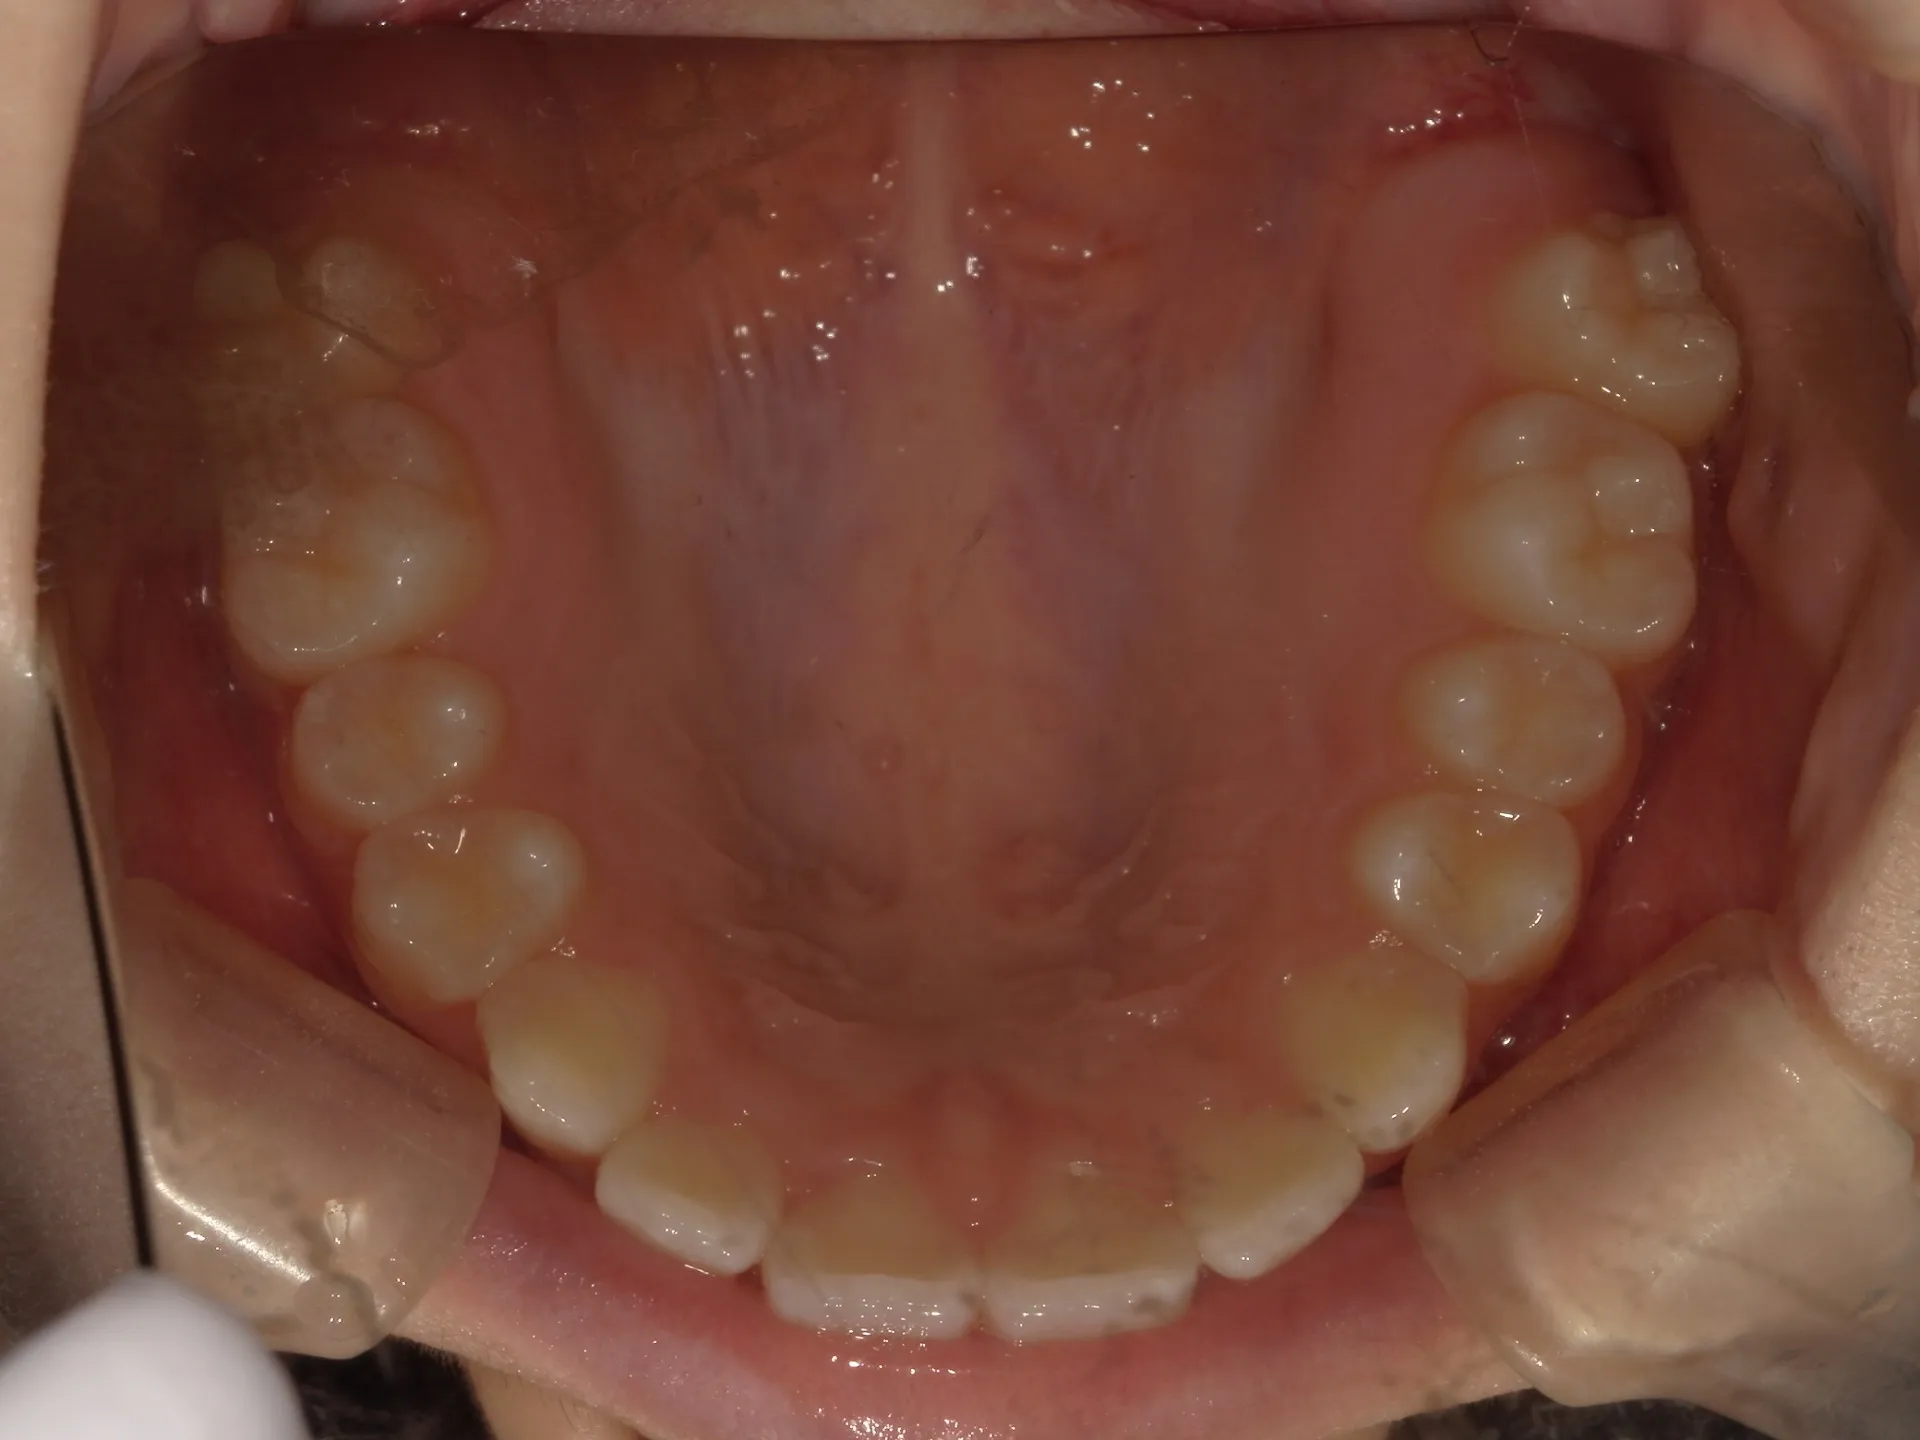

開咬治療前

まず開咬とは、文字通り開いている咬み合わせのことをさします。

分かりにくい方もいるかもしれませんのでもう少し説明すると、今回お見せしている写真では前歯部開咬と呼ばれる開咬です。

臼歯(奥歯)は噛んでいるのに前歯が咬みあわないで開いているという状態のことを前歯部開咬と言います。

さて、治療前の正面観は先ほど述べた通り、前歯部開咬で奥にある舌が見えているのが分かります。